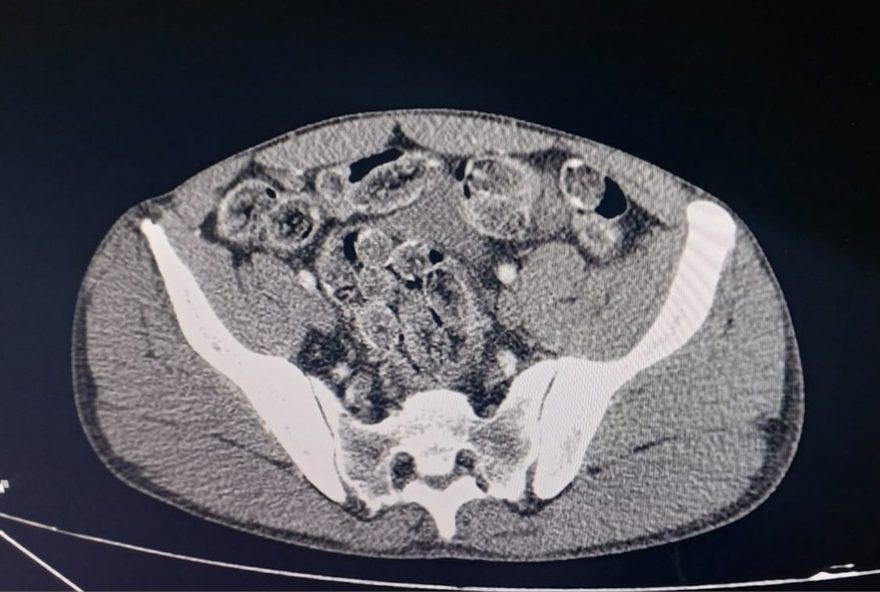

1 de 1 Dois dos detidos ingeriram cápsulas de cocaína e passaram por atendimento médico para expelir a droga. — Foto: Polícia Rodoviária/Divulgação

Os dois homens confessaram ainda ter ingerido parte da droga. Eles foram encaminhados ao Conjunto Hospitalar de Sorocaba (CHS), onde exames constataram a presença de cápsulas no estômago.

Ambos passaram por procedimentos médicos para a expulsão do material e permanecem em observação.